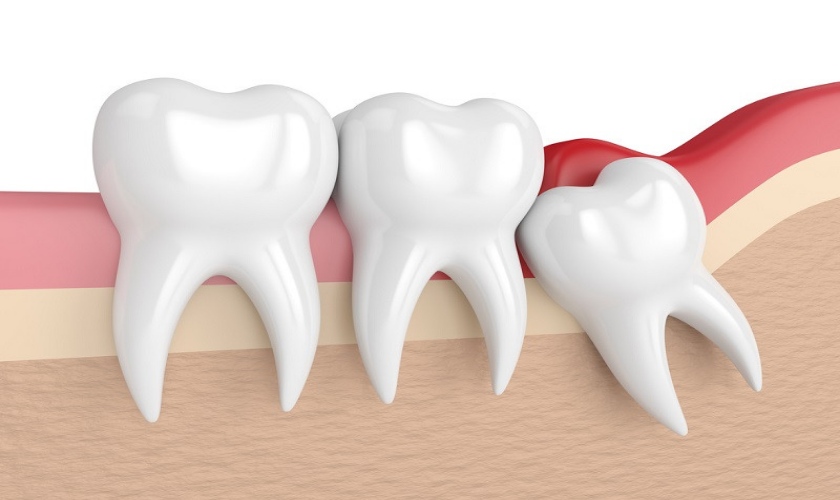

Răng khôn có thể mọc thẳng, mọc lệch, mọc ngầm hoặc mọc kẹt. Trong trường hợp răng khôn mọc khó, bác sĩ có thể chỉ định nhổ răng. Tuy nhiên, có nhiều trường hợp nhổ răng khôn còn sót chân răng. Trong bài viết này, chúng ta sẽ tìm hiểu về nguyên nhân và dấu hiệu nhận biết nhổ răng khôn còn sót chân răng.